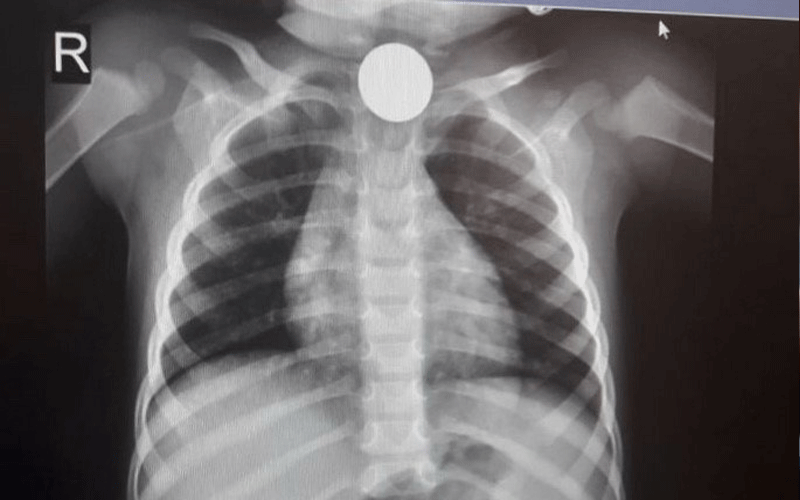

اسعف إلى مستشفى البشير مساء اليوم طفل يبلغ من العمر (4 سنوات) بعد تعرضه للاختناق.

وحسب مصادر طبية لصحيفة نيسان فإن الطفل ابتلع قطعة معدنية "بريزة" تسببت له بالاختناق، خلال تواجده في منزل ذويه في منطقة عين الباشا.